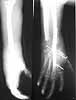

This is the case of an young adult involved in an industrial accident. Subtotal amputation with lots of tissue loss. Both radial and ulnar artery divided with loss of segments. Both median and ulnar nerves divided with loss of segments.All flexor tendons divided with loss of tissue. Extensors to thumb divided with loss of tissue. Extensor digitorum in continuity. Loss of segment of radius. Loss of carpal bones. Skin bridge on ulnar border intact with a collateral blood supply to hand. What will be the consensus? Amputation with early prosthesis or limb salvage with all the attended risks and prolonged and multi staged procedures with unpredictable outcome and finally a possibility of a cosmetic hand? Will be happy to know the views.

Severe bone loss. Thumb fracture. Missing most of wrist joint. terrible nerve injury. Tremendous soft tissue defect.

I agree. I think that this case illustrates well the concept of "zone of injury". These presumably acute trauma films do not adequately convey the full extent of the damage. Very interested to hear what other Hand and Upper Extremity folks think also.